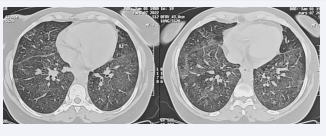

Chest CT scan showed bilateral ground-glass opacities associated with reticulations giving a “crazy paving”appearance (Figures 2).

Bilateral ground-glass opacities associated with reticulations  giving a crazy paving aspect.

Figure 2: Bilateral ground-glass opacities associated with reticulations giving a crazy paving aspect.